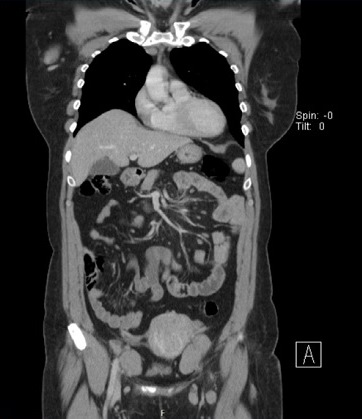

Foi efetuado o estudo por tomografia computorizada (TC) cervical, torácica e abdómino‑pélvico (Figura 8), que identificou adenopatias nas cadeias linfáticas supra e infradiafragmáticas nível as maiores ao longo dos compartimentos mediastínicos, a maior com 36‑300mm; cadeias lombo‑aórticas (35x20 mm) e regiões ilíacas (49x29 mm).

Figura 8 Estudo por tomografia computorizada (TC) cervical, torácica e abdomino ‑ pélvico

No que respeita ao estadiamento, a tomografia computadorizada (TC) é o exame de eleição no LF. O exame por TC deve incluir a região cervical, tórax, abdómen e pélvis. PET‑CT poderá ser recomendada em caso de suspeita de transformação para linfoma agressivo ou para confirmar doença localizada.